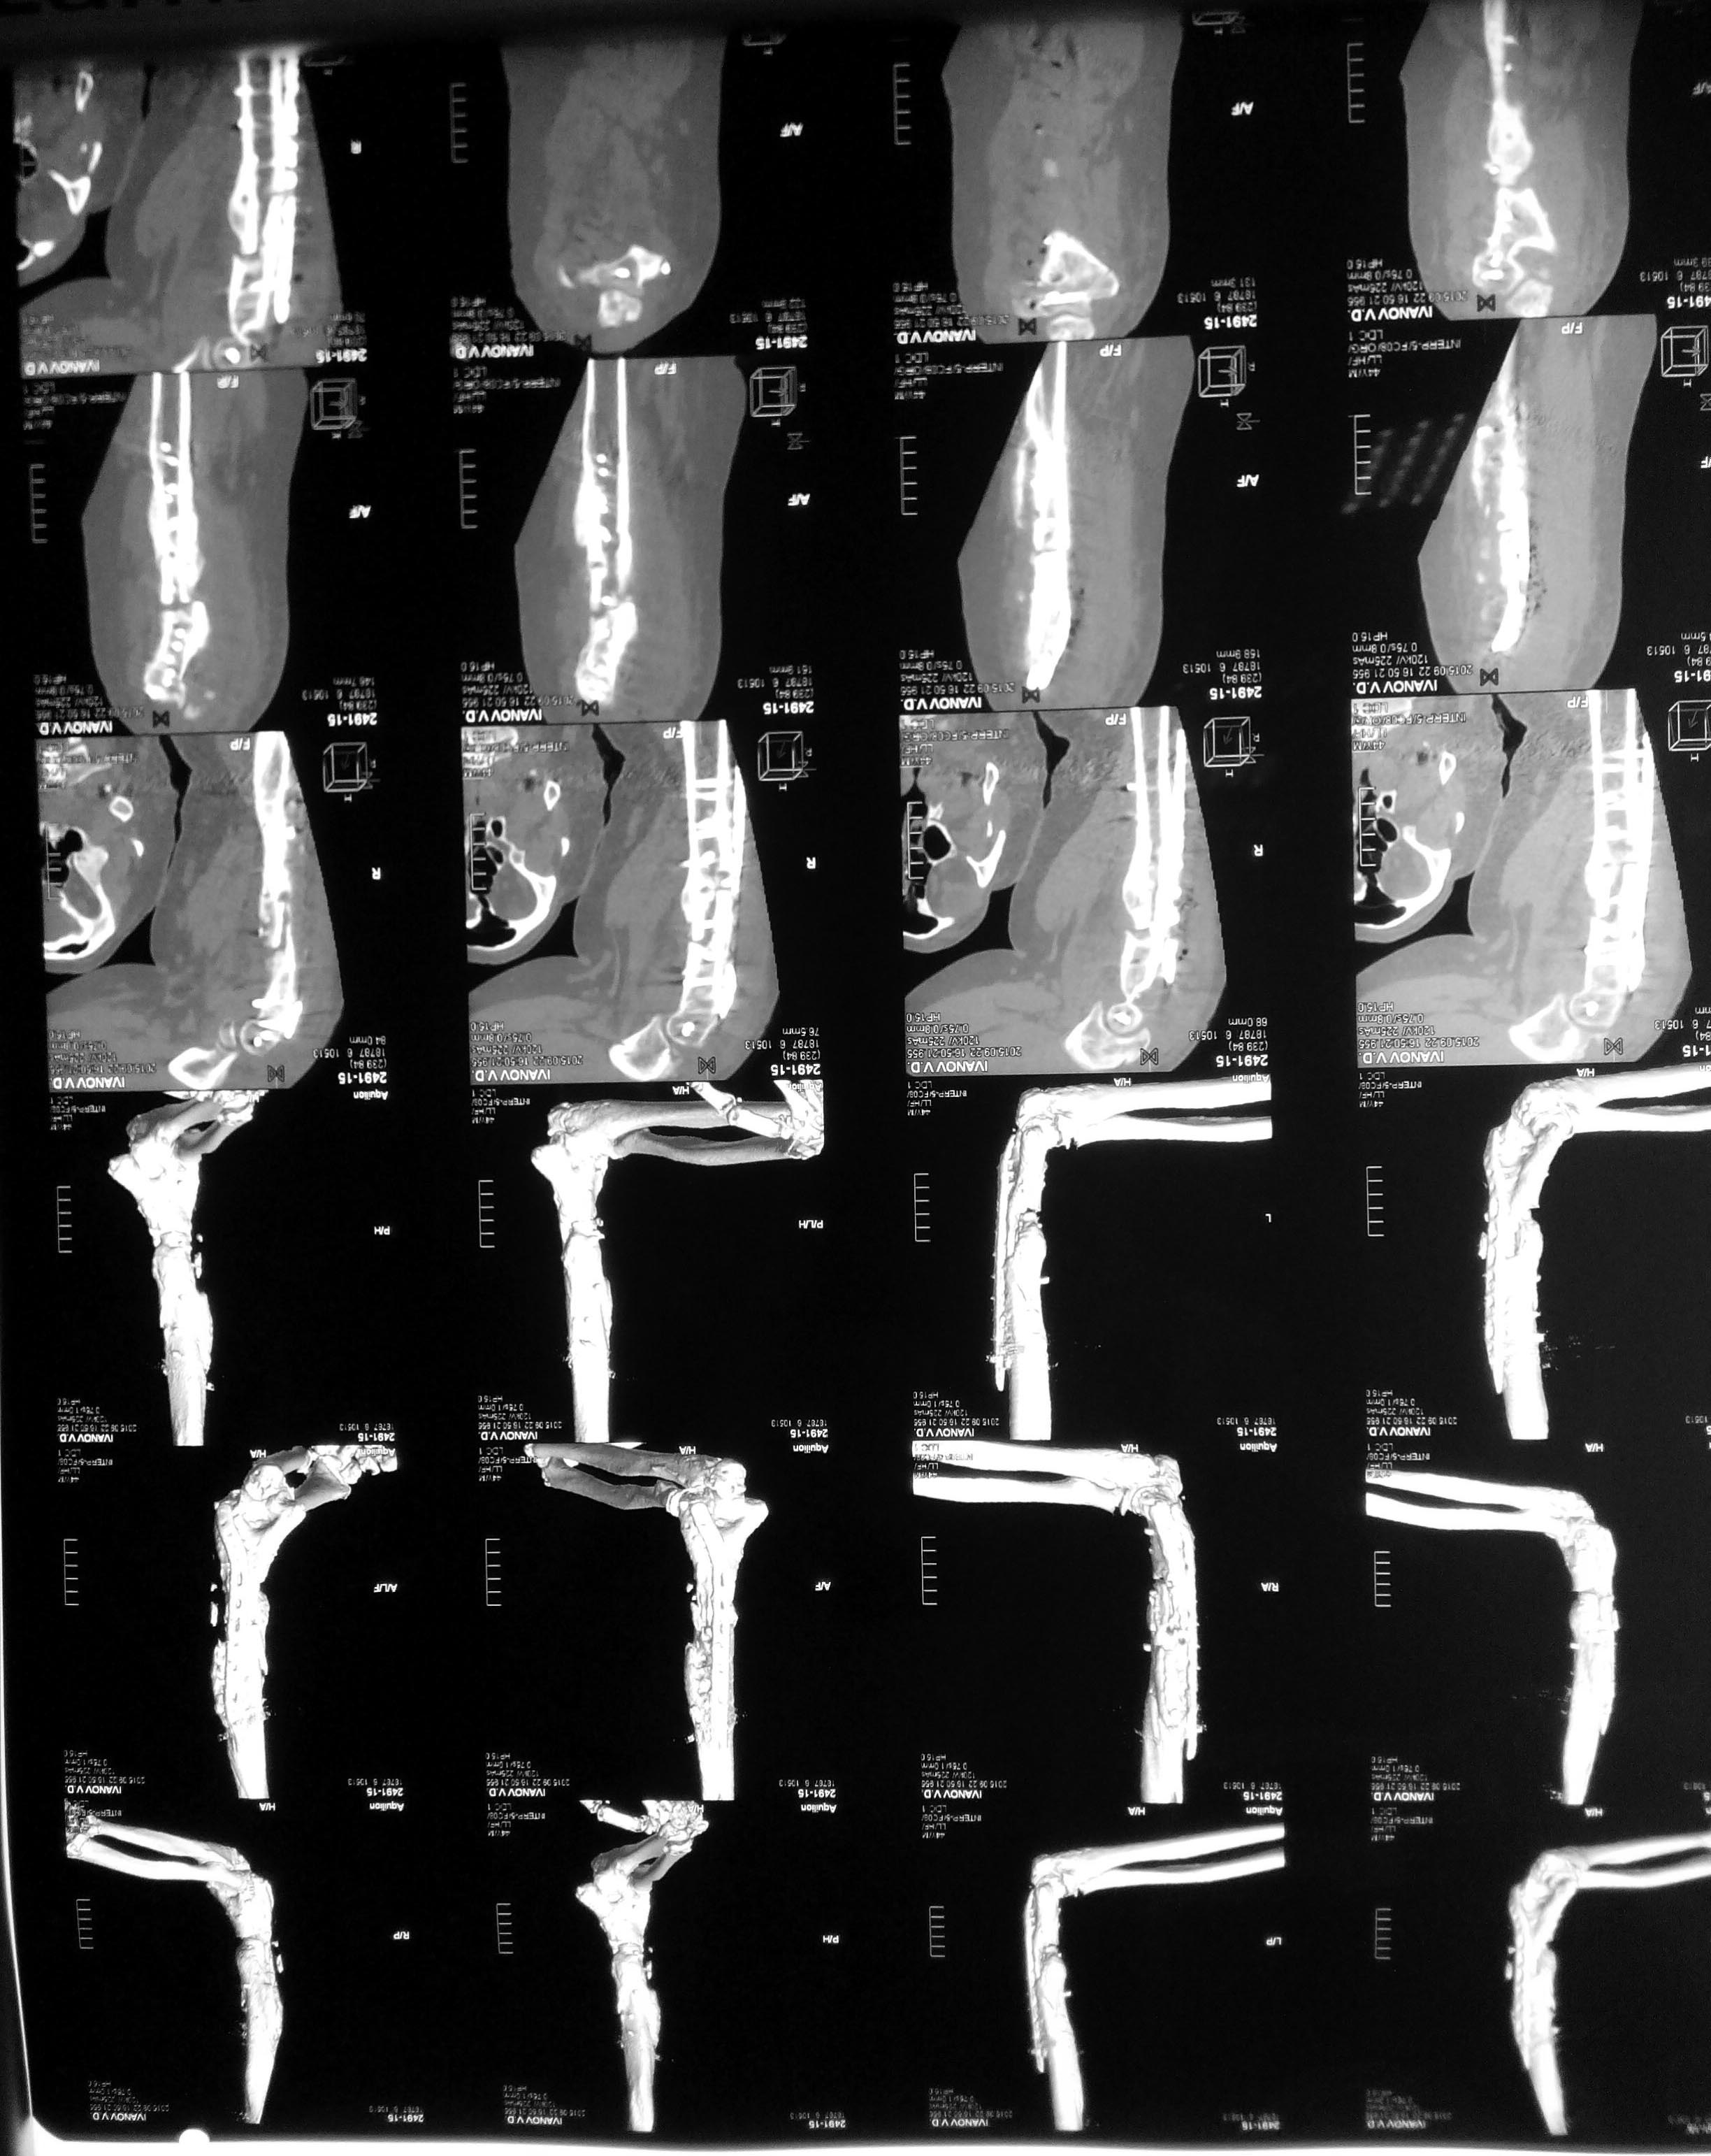

Уважаемые коллеги, хотелось бы услышать вашего мнения по поводу непростого случая несросшегося перелома плечевой кости. Пациент 44года в 2013г закрытый многооскольчатый перелом дистального отдела правой плечевой кости. Остеосинтез пластинами в одной из столичных клиник. В п/о периоде нейропатия лучевого и локтевого нервов, за 10 месяцев лучевой полностью восстановился, локтевой почти - небольшие парастезии в мизинце остались. Обратился ко мне летом 2015г (по совету общего знакомого), до этого обращался в учереждение где был выполнен остеосинтез, но в силу ряда причин не пожелал там оперироваться (кстати предлагалось только удаление металлофиксаторов). Пациент без вредных привычек (разве что переедание), из сопутствующей патологии ожирение (вес 160 кг рост 190см), сахарный диабет (невысокие цифры).В августе 2015г удаление металлофиксаторов, невролиз лучевого нерва, реостеосинтез (той же) пластиной, но в положеном задне-латеральном положении. При операции удалено около 50 куб. металлоза, при ревизии в месте несращения были подозрительные творожистые включения, но кость выглядела здоровой,все многократно промывал антисептиками, иссечены рубцы, края отломков адаптированы друг к другу по типу замка - зона контакта большая, суммарно кость укорочена около 1,5 см. Перед операцией планировал ставить 2 пластину медиально, но до операции консультировался с более опытными коллегами и ставить вторую пластину не рекомендовали, все же заказал, но не поставил... операция заняла в целом 7,5 часов то ли устал, то ли действительно фиксация показалась достаточной учитывая характер сопоставления отломков (ну не суть важно что сделано то сделано). Был установлен дренаж, но наследующий день он забился - удалил, опасаясь инфицирования довольно агрессивно промывал хлоргексидином, на 5 сутки на коже нижней трети плеча по наружной поверхности появился пузырь 10 на 10 см, промывать перестал. Рана зажила первичным натяжением. Дефект кожи после фликтены постепенно заживает (от пересадки кожи пациент отказался). После операции нейропатия лучевого нерва (целостность сомнению не подвергается был выделен весь) за 2 месяца значительная положительная динамика. Иммобилизирован на косынке. В сентябре ниже локтевого отростка появилась небольная безболезненная припухлость по ходу рубца, была вскрыта и получен гной (со слов коллеги я был в отпуске), через 4 дня я видел рану гноя не было отделяемое серозное больше похоже на синовиальную жидкость (предполагаю что идет от локтевого отростка к которому было пришито сухожилие трицепса тисорбом они часто текут по личныим наблюдениям, но не факт...), неоднократно посев роста нет, кровь спокойная, температуре нет соответственно. 2 месяца после операции (22.09.15г) КТ контроль - все стабильно. Две недели назад разрешил иногда снимать косынку но рукой не пользоваться. Неделю назад пациент стал говорить что появился хрукт. Рентген контроль - перелом 2х винтов нестабильность вторичное смещение. Предварительно планирую брать на ревизию удалить винты с проксимального отдела, репозиция остеосинтез и дополнительно медиальная реконструктивная? пластина.

1. По представленной информации не совсем понятен смысл выполненной вами в августе операции. На передне-задней рентгенограмме убедительных признаков несращения нет. Было бы неплохо выложить вторую проекцию - возможно она действительно продемонстрирует несращение. Прикрепленная КТ не читаема (и наверное это КТ за сентябрь). (Кстати желательно уменьшить размер файлов согласно инструкции на сайте - очень долго грузятся).

Может не так хорошо видно, но ВСЕ винты были сломаны и из 7,5 часов 5 ушло на удаление и невролиз, может не так хорошо видно но ВСЕ винты были сломаны, все было в грубом рубцовом конгломерате и металлозе, промывал хлоргекс и бетадином, фликтеной назвал условно потому как предполагаю что из-за выраженного отека и плюс дополнительно накачивал промывая остро появился пузырь отслоивший кожу (как его по другому назвать не знаю), насчет зачем полез, да почему то многие считают что пациенту нужно было ждать пока не сломается пластина, компрессию дал, между фрагментами винт поставил на снимке видно(хотя думаю не стоило он и сломался). И снимок за 6 месяцев до последнего где было только 2 винта сломано выкладываю.

К сожалению не могу выложить кт до операции, т.к было на диске, там значительный дефект в зоне несращения и свободно болтающиеся два винта. Уважаемые коллеги, я прежде всего хотел услышать мнения по поводу поставленных вопросов. Рассуждать о целесообразности реостеосинтеза считаю бессмысленным во первых потому что это уже свершившийся факт, во вторых потому что ни меня ни пациента в обратном никому не убедить. По поводу чистоты операционной - она близка к идеальной, у нас небольшая частная клиника на 10 коек,где преимущественно занимаемся эндопротезированием суставов конечностей, исправлением кривизны и длины конечностей,артроскопией и реже остеосинтезами,"грязных" пациентов и посетителей не бывает в принципе, гной тоже не берём. А касательно того что зачем лезть рискуя испортить репутацию и быть оплеванным коллегами - наверно прежде всего нужно исходить из интересов пациента а не собственной безупречности. Я понимаю что были ошибки и понимаю какие, мне не стыдно в этом признаться, но уверен что все же доведу пациента до сращения и выздоровления. Поэтому и обратился сюда за советом по поводу поставленных вопросов.

Касательно диагноза несращения ну незнаю как кому, но мне для того что бы несоммненно определиться что имеет место несращение было достаточно представленных пациентом (и выложенных мною ) двух снимков от ноября 2014г и августа 2015г в прямой проэкции (других у него не было). МСКТ делал чтобы оценить смогу ли установить штифт - подумал смогу - при операции понял что нет.